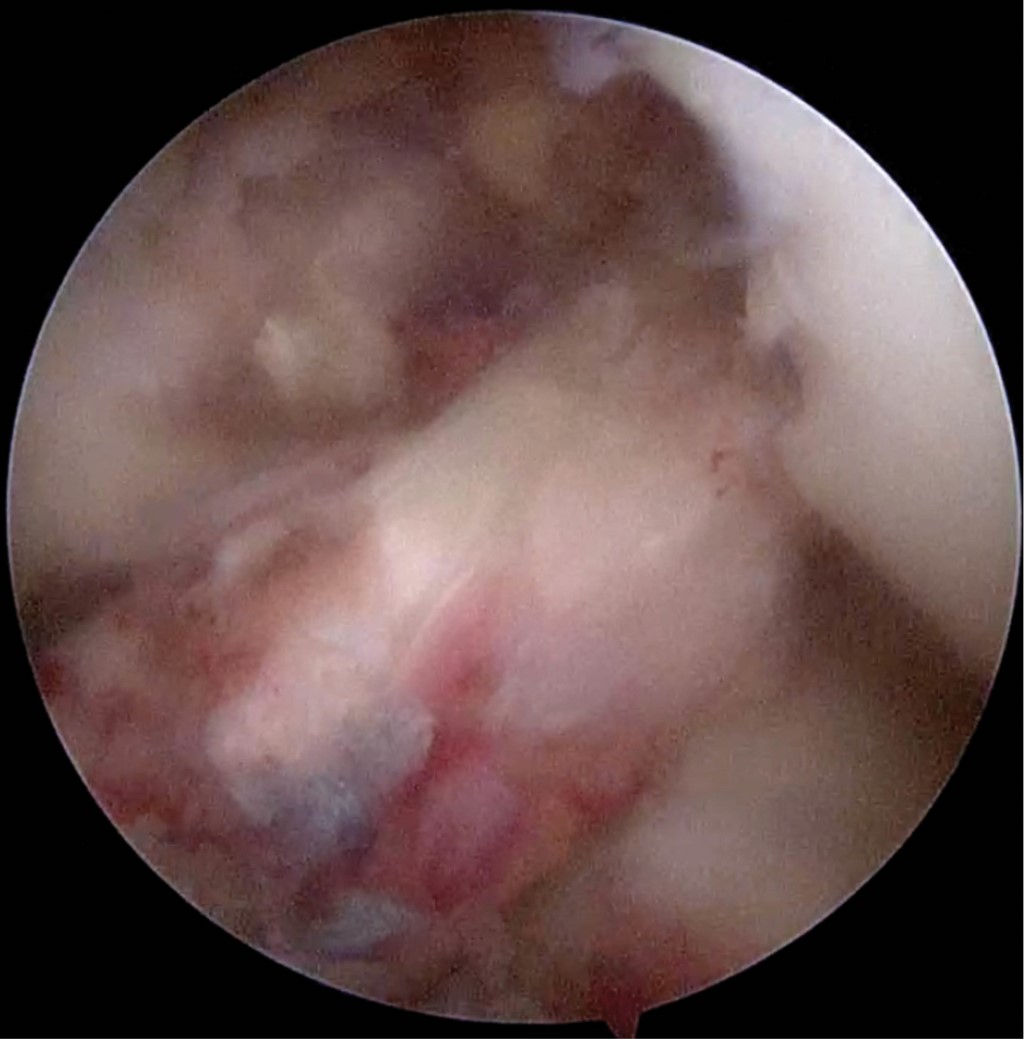

Introduction: Anterior cruciate ligament injuries are common, however, tibial avulsions in adults are rare. The gold standard continues to be reconstruction either by allograft or autologous graft. Primary repairs in femoral side lesions have been reported in recent years by bioabsorbable anchors. Case report: We present the case of a primary repair of anterior cruciate ligament due to tibial avulsion in a patient 19 years after presenting direct trauma with added lesions of posterior cruciate ligament and posterolateral corner. Primary repair was performed by trans-tendon portal with suture of the anterior cruciate ligament crossed by FiberTape and FiberWire with a SwiveLock anchor (4.75 mm) in tibial footprint. Results: Twelve months after surgery is with independent gait, full range of movement, with clinical rating scales, Tegner before injury and post-injury at 6, Lysholm 91, 73.6 subjective IKDC, objective IKDC in C and EQ-5D 0.79. Conclusion: Fixation with bioabsorbable anchor is possible in the avulsion of the post-traumatic tibial spine.

Figure 4